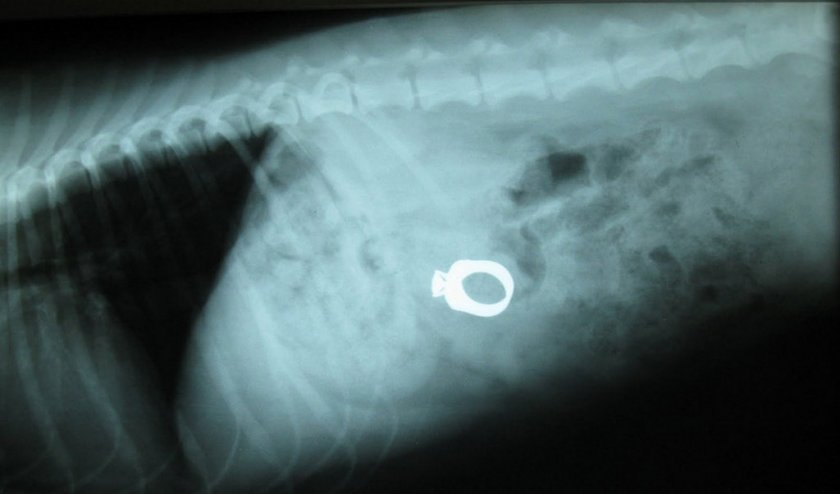

Травмы и попадание инородного предмета

Щенки во время игры часто заглатывают предметы больших размеров. Они могут застревать в органах пищеварения. Болезненные симптомы в животе возникают в результате травмы спровоцированной инородным предметом. В результате может возникнуть воспаление желудка или кишечника. Такое животное отказывается от еды, имеет угнетённое состояние, повышенную температуру, рвёт, горбится при дефекации, в кале могут присутствовать следы крови. Если инородное тело не удалось извлечь, вызывая рвоту у животного, то прибегают к хирургическому вмешательству.

Как проходит диагностика

После оказания первой помощи животное следует отвезти в клинику. Врач осмотрит пса, проведёт пальпацию брюшной полости, назначит анализы кала, мочи и крови, УЗИ, возможно рентген, и определит лечение.

Важным фактором в установлении правильного диагноза является рассказ владельца о начале заболевания и проявлении симптомов.